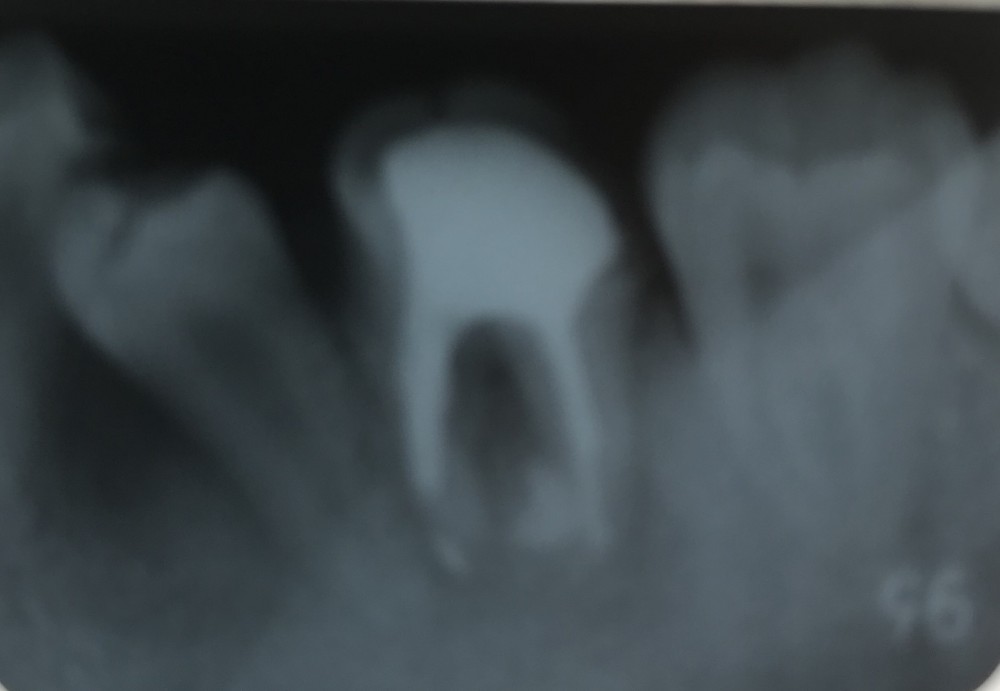

下は左下6根管充填の画像です。初診時から2ヶ月後撮影。

左下E抜歯してから2ヶ月程度経過しているため、左下5の萌出が良好であるのも確認できます。